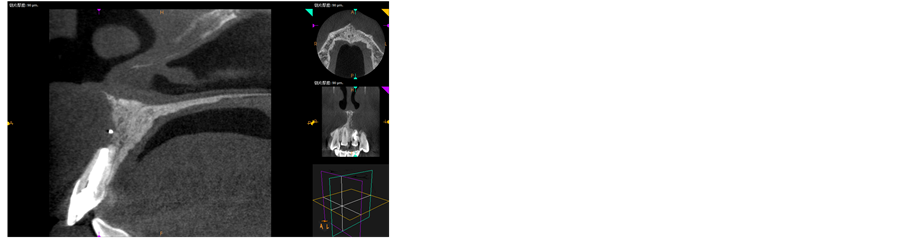

mm (Figures 4-6). 3) Scratch the apex and wash it with normal saline. Restore and suture the mandibular with minocycline smeared in partial (Figure 7). 4) Post-operative CBCT shows that root filling was improved and the resistant projection of agglomerate at apex disappeared (Figures 8-9). 5) Fistula disappeared 1 week after operation (Figure 10). 6) Intracoronal bleaching was conducted and then medical prescription was changed twice in follow-up visit. The color of 21st tooth became 11 and 12 with resin repair at the incisal margin of 21st tooth. 7) The color change of bleaching opisthosoma is relatively obvious than that in neck. The color of tooth neck is dark. The protective screen was established for the third bleaching. Four days later, further consultation was conducted with color of tooth neck improved. The patient was satisfied (Figure 11). 8) 1, 3, 6 and 12 months after operation, further consultation was conducted in follow-up (Figure 12).

Figure 8. Postoperative CBCT showed that the root apex had no foreign matter root filling.

Figure 9. Preoperative X-ray films.